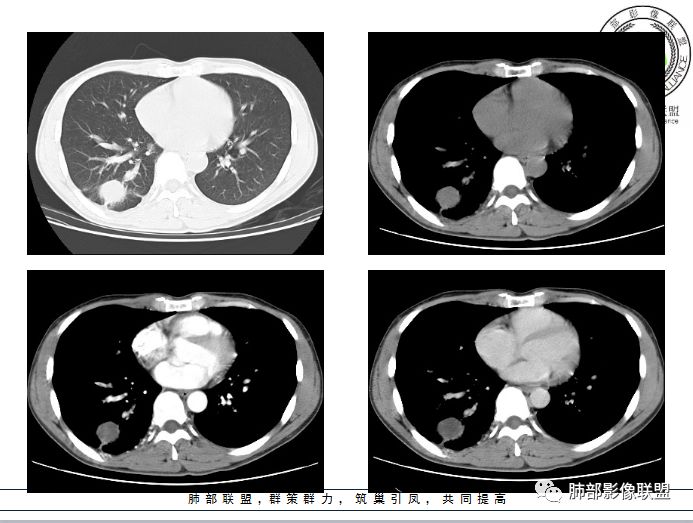

右肺下叶囊性病变,边缘光滑,薄环状强化,内壁较光滑

血管贴边

周围多发长索条

远端有斑片状条带状高密度影,周围肺气肿

附近胸膜增厚,内有血管影

南大病变影像分析:

这个病变和大家所想有些差异,这个图像还是不够薄,但是

第一,看支气管,有一条支气管从病变边缘走过,有一条支气管在病灶近端堵塞;说明病变和支气管有关系,一般情况下支气管堵塞应该考虑炎性病变或恶性肿瘤才可以符合,不符合良性肿瘤,当然肺囊肿也可以,因为它是先天发育变异的。

第二,看强化幅度,内无强化,但是我担心图像并不够薄,目测观察有所偏差,但是现可见薄壁样强化;从这个角度考虑,良性肿瘤就不符合了,如PSP就不太支持了,这个病变远端有分叶、有小尾巴,周围有索条状影,除非PSP合并感染,二元论,否则单纯PSP周围不会有这种表现。

第三,病变旁边胸膜区域有增厚,似乎有些血管增粗,虽然这不是隔离征好发区域;它应该偏内侧一点,但是我们应该最好有重建血管先排除隔离征;从所给图片看,病灶具体走形外面没有看见血管进入,因为是囊性病变嘛。